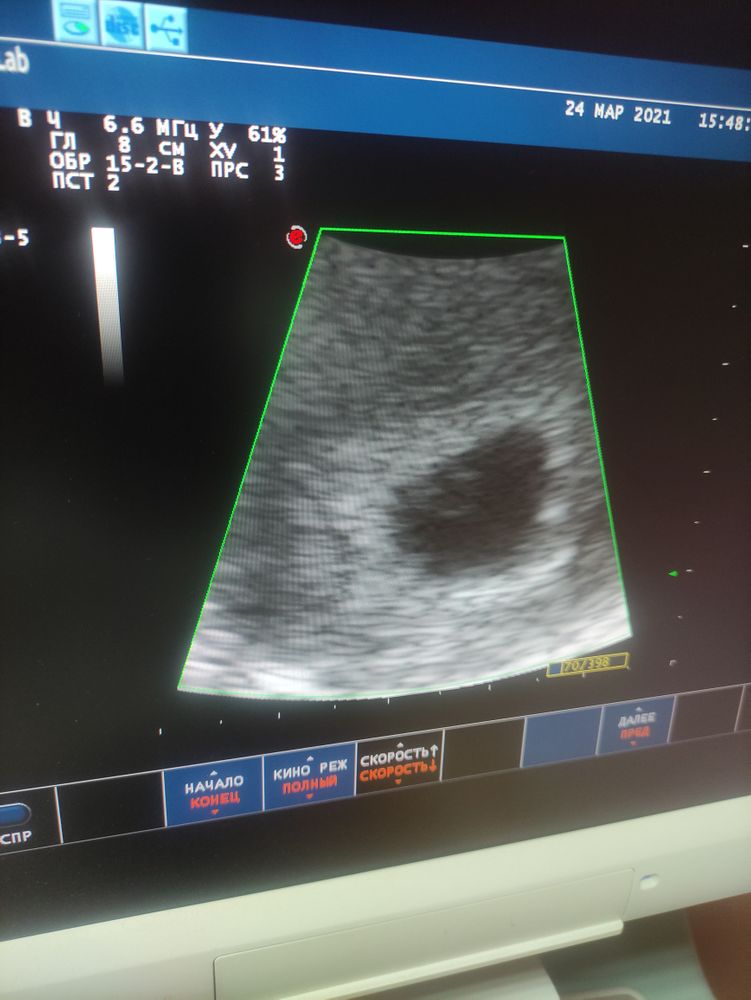

Девочки кто разбирается.это норм по УЗИ все ?

посмотрите пожалуйста по срокам. Нормальное ли КТР сердечка ??? 16.03 не было ещё сердечка ...плодное яйцо было 11 мм сейчас уже богатырь по моему. Она просто толком ничего не объяснила)))

Отличница, извините... Срок 7 недель по последним дате месячных... А так написали 5 недель. Ктр 4.8 мм

Оля Горохова, ктр соответсвует 7 неделям, у меня такой же был, 4,5) говорили что все ок

Отличница, я спросила за сердечко она сказала бьётся тип но слабо ещё . Показала где оно тип бьётся но я там ничего не увидела ))) на бумажке написано просто сердцебиение+